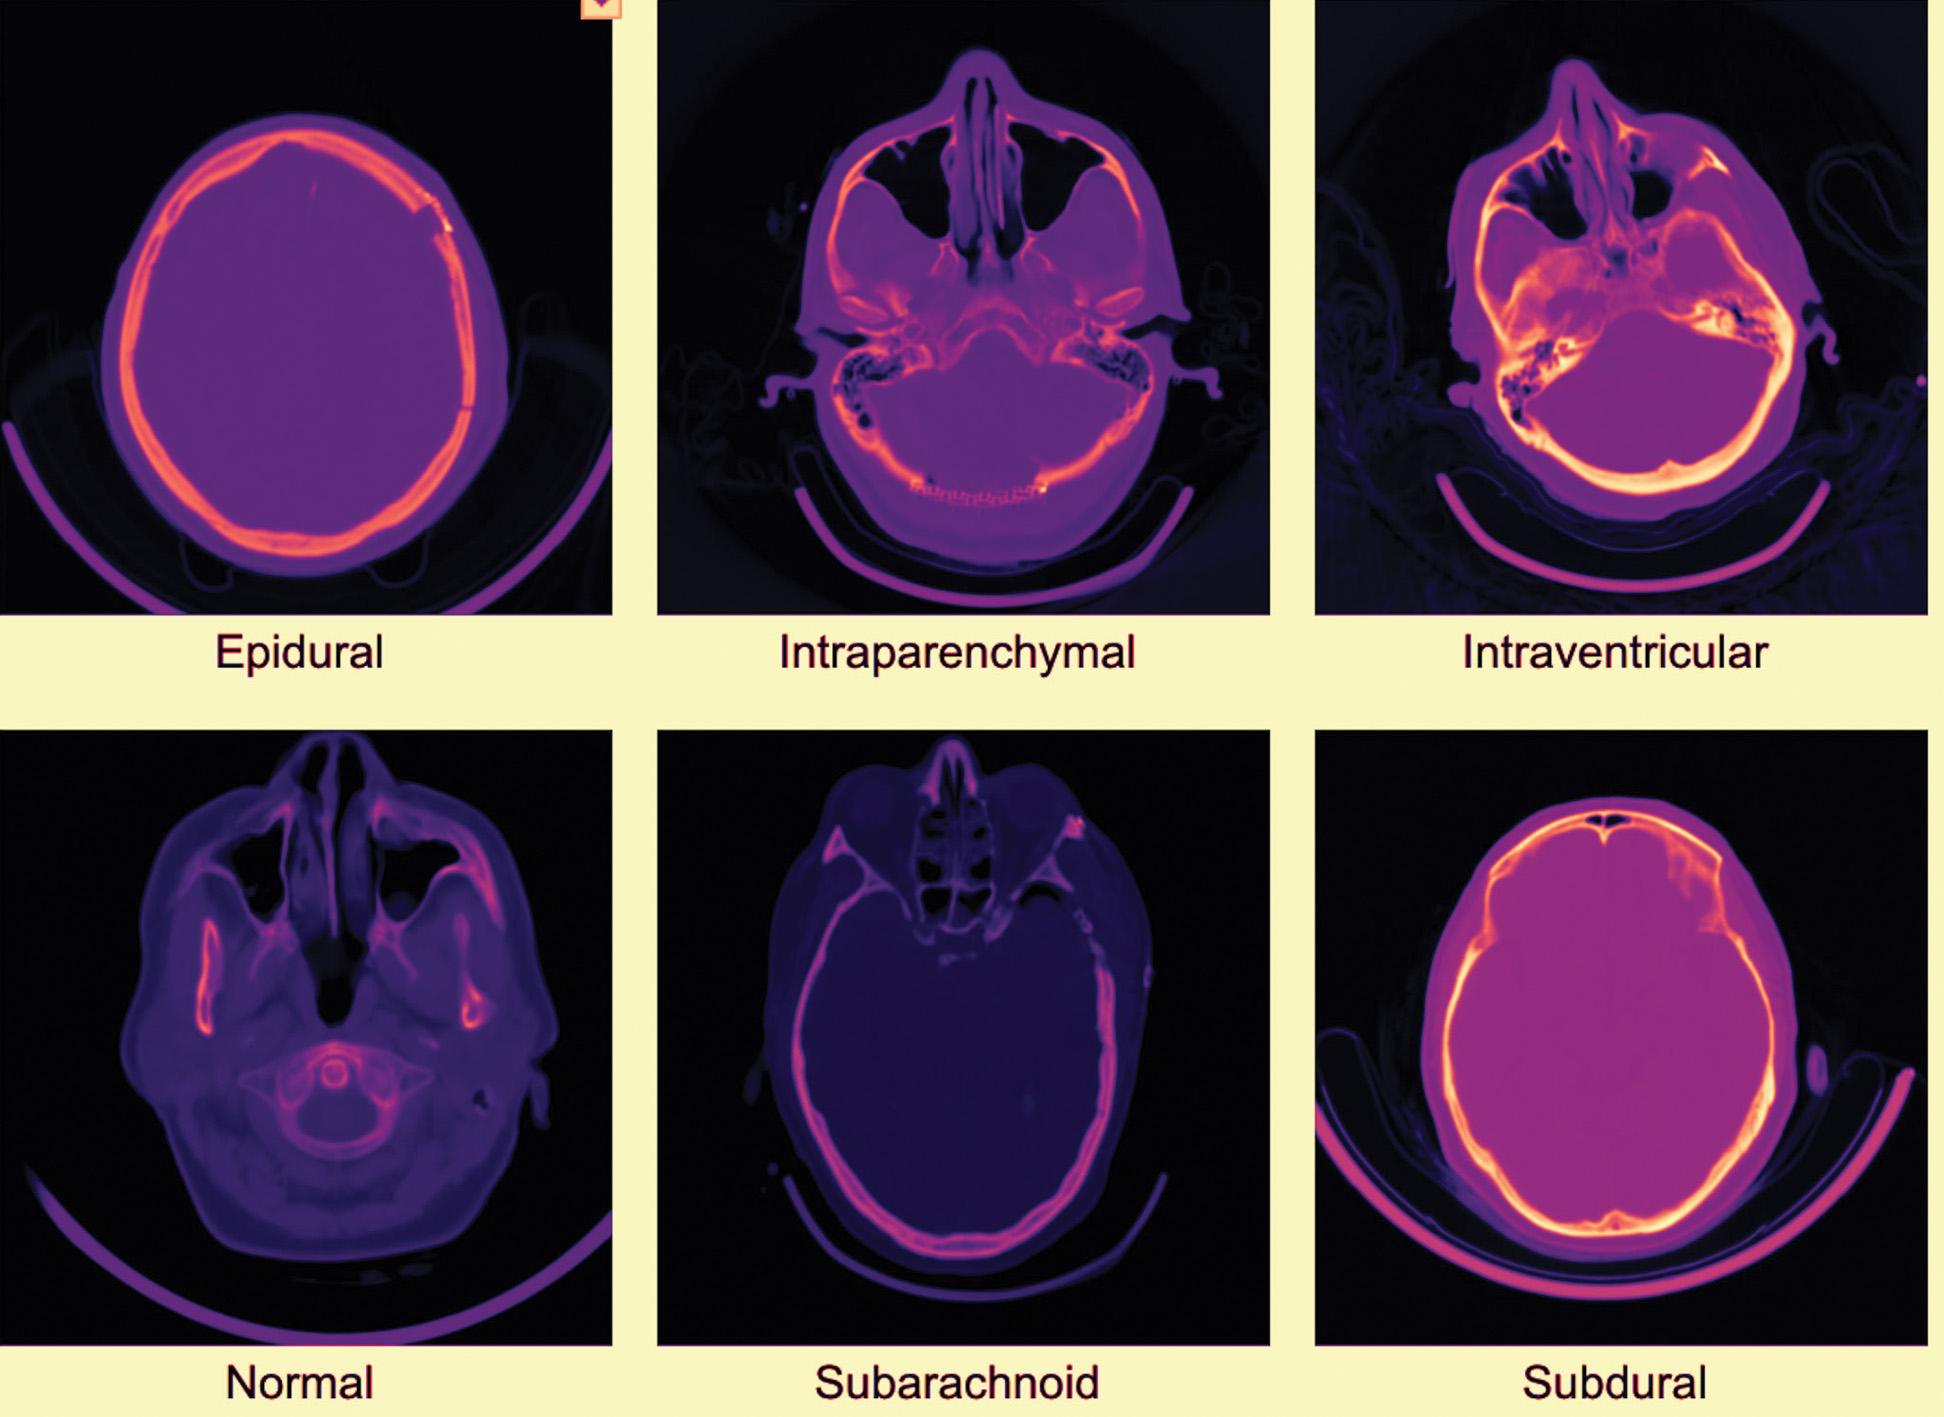

Intracranial Hemorrhage (ICH) is one of the most clinically significant consequences of TBI and occurs when blood gathers in or around the brain due to traumatic injuries to blood vessels. ICH does not exist as an entity, but it is a continuum of various categories of hemorrhages, some of which include epidural, subdural, subarachnoid, intraparenchymal, and intraventricular hemorrhages. Each of these subtypes implies a different clinical implication. When it comes to skull fractures, the epidural hemorrhages can grow and require urgent neurosurgical intervention. Subdural hemorrhages, in turn, may proceed at a slower pace, yet they are also associated with a high mortality rate in the case of failure to treat them. Subarachnoid bleeding is associated with the risk of vasospasm and delayed ischemia, and intraventricular bleeding could lead to the blockage of cerebrospinal fluid channels and consequently to hydrocephalus. The intraparenchymal hemorrhages that occur in brain tissues may cause devastating focal deficits depending on their localization. In light of such multiplicity, the appropriate categorization of ICH subtypes is critical to selecting the appropriate clinical pathway and prioritizing interventions in acute care.

The dataset used in this study was self-collected from Shriman Hospital, Jalandhar, under the supervision of certified radiologists and following institutional ethical guidelines. The acquired CT scans contained six categories of intracranial conditions: epidural hemorrhage, intraparenchymal hemorrhage, intraventricular hemorrhage, subarachnoid hemorrhage, subdural hemorrhage, and normal scans. To address class imbalance and increase the dataset size, we applied structured augmentation techniques, including rotation, intensity variation, cropping, and Gaussian noise injection. These operations resulted in a balanced dataset of 60,000 CT slices, with approximately equal representation across all six classes. To support reproducibility and open research, the final augmented dataset has been publicly released on the Mendeley Data repository. No external hospital data or multiple-source aggregation was used in this study; all raw data originated from Shriman Hospital, Jalandhar. The dataset employed in this study comprised 60,000 head CT images, evenly distributed across six clinically relevant categories of intracranial hemorrhage: epidural, intraparenchymal, intraventricular, subarachnoid, subdural, and normal (ne). Each class contained 10,000 images, ensuring perfect balance and preventing class-specific bias. Representative CT slices for each class are shown in Fig. 1.

Fig. 1. Examples of head CT scans for each of the six classes in the dataset.